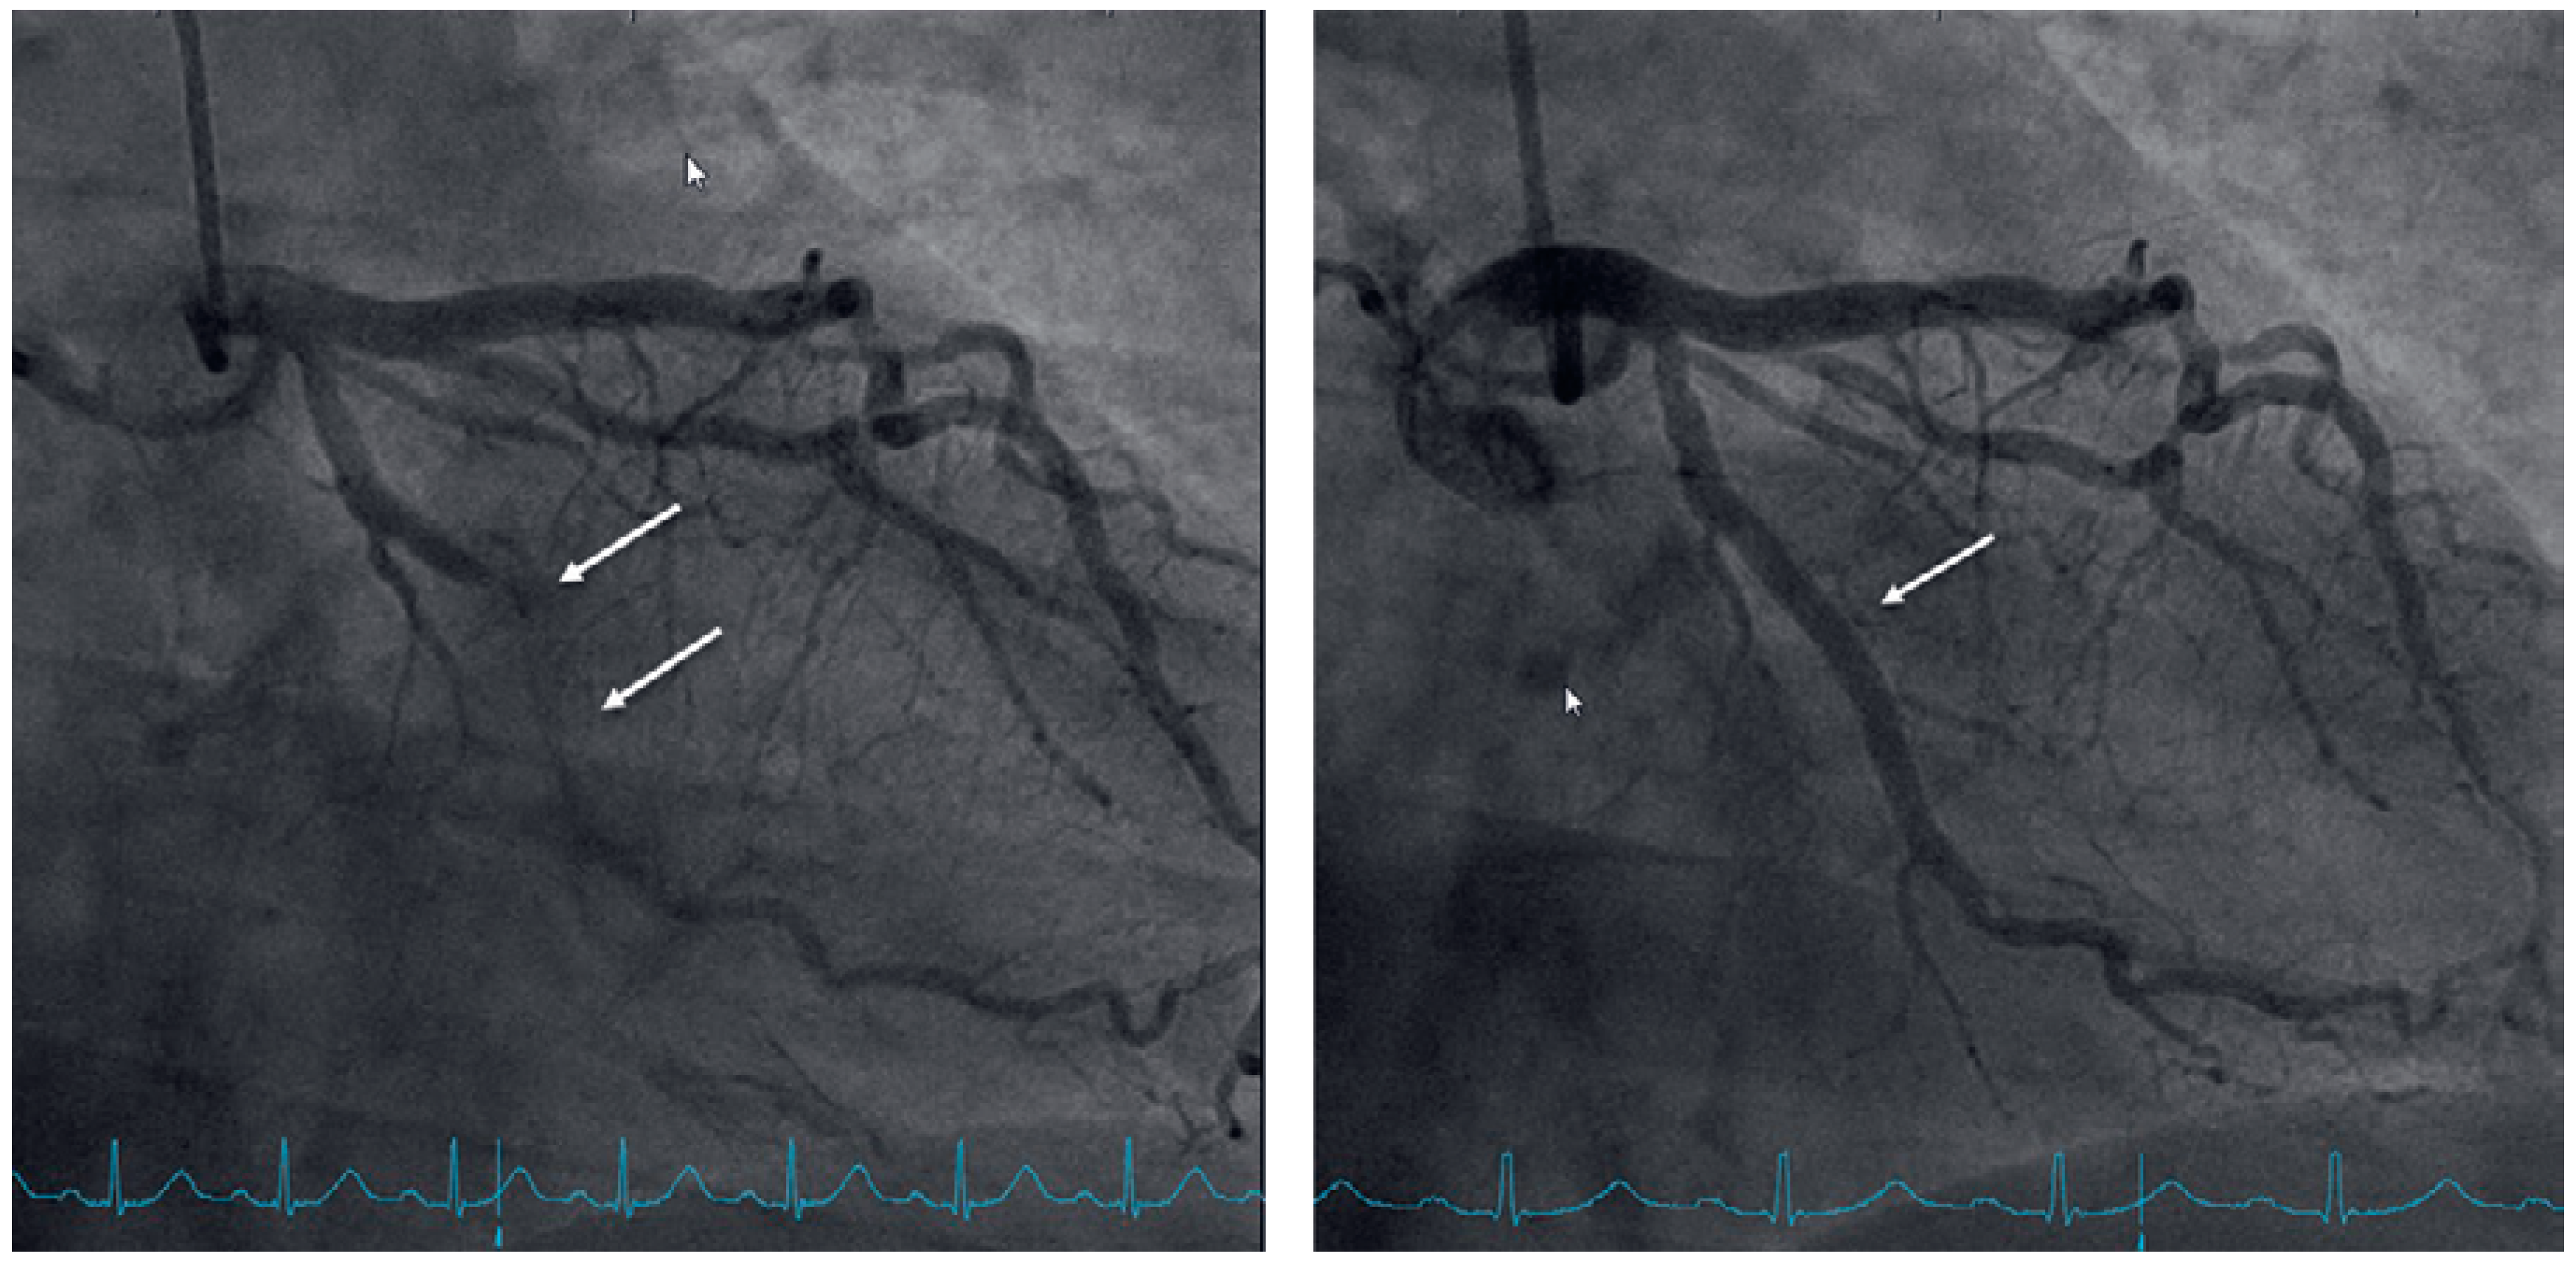

Flecainide Induced ST Segment Changes Can Mimic Pathological ECG Changes in Patients Undergoing Exercise Testing: A Case Report

Case presentation